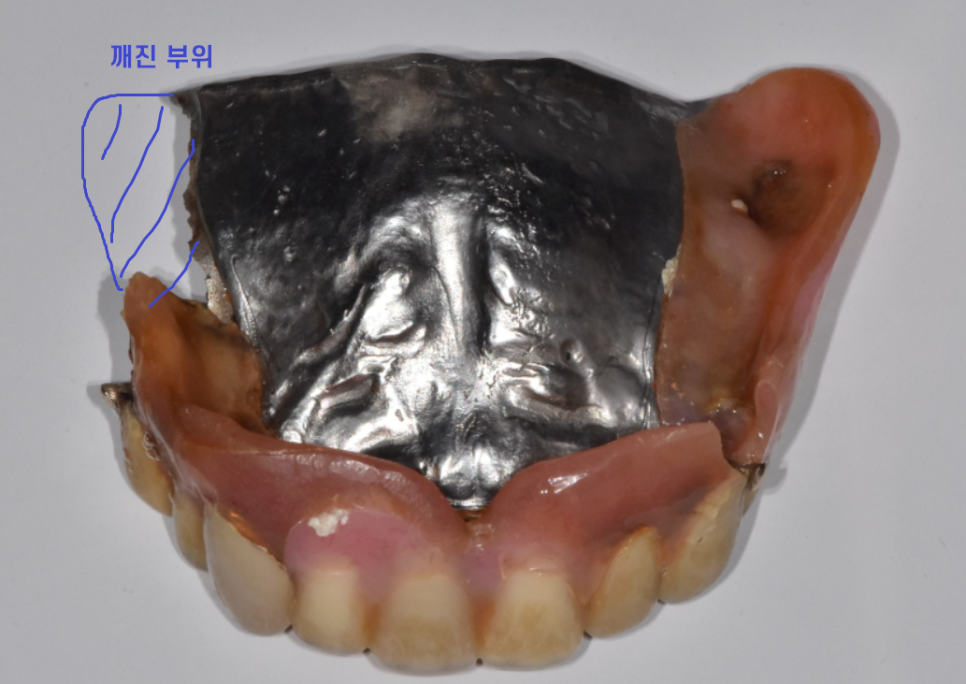

틀니 수리해주세요

230714

당뇨로 인하여 일찍부터 치아를 다수 상실하셨다는 어르신

그동안 틀니를 사용하고 계셨는데

오래 사용하다보니 낡기도 하였지만

떨어트렸다가 틀니가 깨지셨답니다.

틀니를 수리하시기 위하여

고덕역 치과를 방문해주셨는데요.